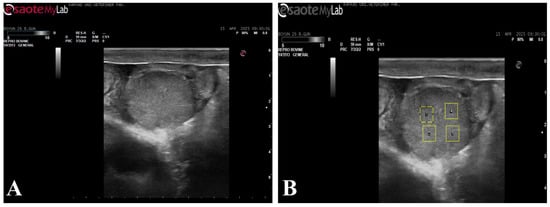

Figure 1.

B-mode ultrasonographic image of the corpus luteum used for echotexture analysis. (A) B-mode ultrasonographic image of the corpus luteum; (B) The same image showing the placement of four regions of interest (ROIs) selected for ImageJ-based grayscale and homogeneity analysis.

2.5. Echotexture Analysis

For echotexture analysis, the recorded images were transferred to a digital environment in bitmap (BMP) format and converted to grayscale prior to analysis. The images were analyzed using ImageJ (v. 1.52, NIH, ABD) software. In each image, four artifact-free regions of interest (ROIs; 35 × 35 pixels) (Figure 1) covering the ovary and endometrium were defined. ROI size was selected in accordance with previously published echotextural analyses employing similar ROI dimensions for standardized image evaluation [12,19]. For corpus luteum analysis, ROIs were placed within homogeneous luteal parenchyma while avoiding cavitations, peripheral borders, and acoustic shadowing artifacts. For uterine assessment, ROIs were positioned within the endometrial layer at comparable anatomical locations, avoiding luminal fluid, folds, and artifacts. ROI placement was performed using consistent anatomical landmarks and standardized image planes to ensure repeatability between examinations. A total of 12 ROIs were evaluated for each animal. Corpus luteum mean gray value (CL-MGV), uterine mean gray value (UT-MGV), as well as corpus luteum homogeneity (CL-HOM) and uterine homogeneity (UT-HOM) parameters, were calculated and used in the statistical analyses. Image analysis and parameter extraction were performed by the same investigator using standardized procedures. Blinding to group allocation was not applied due to the nature of repeated ultrasonographic measurements; however, consistent acquisition settings and predefined analysis protocols were used to minimize potential observer bias.